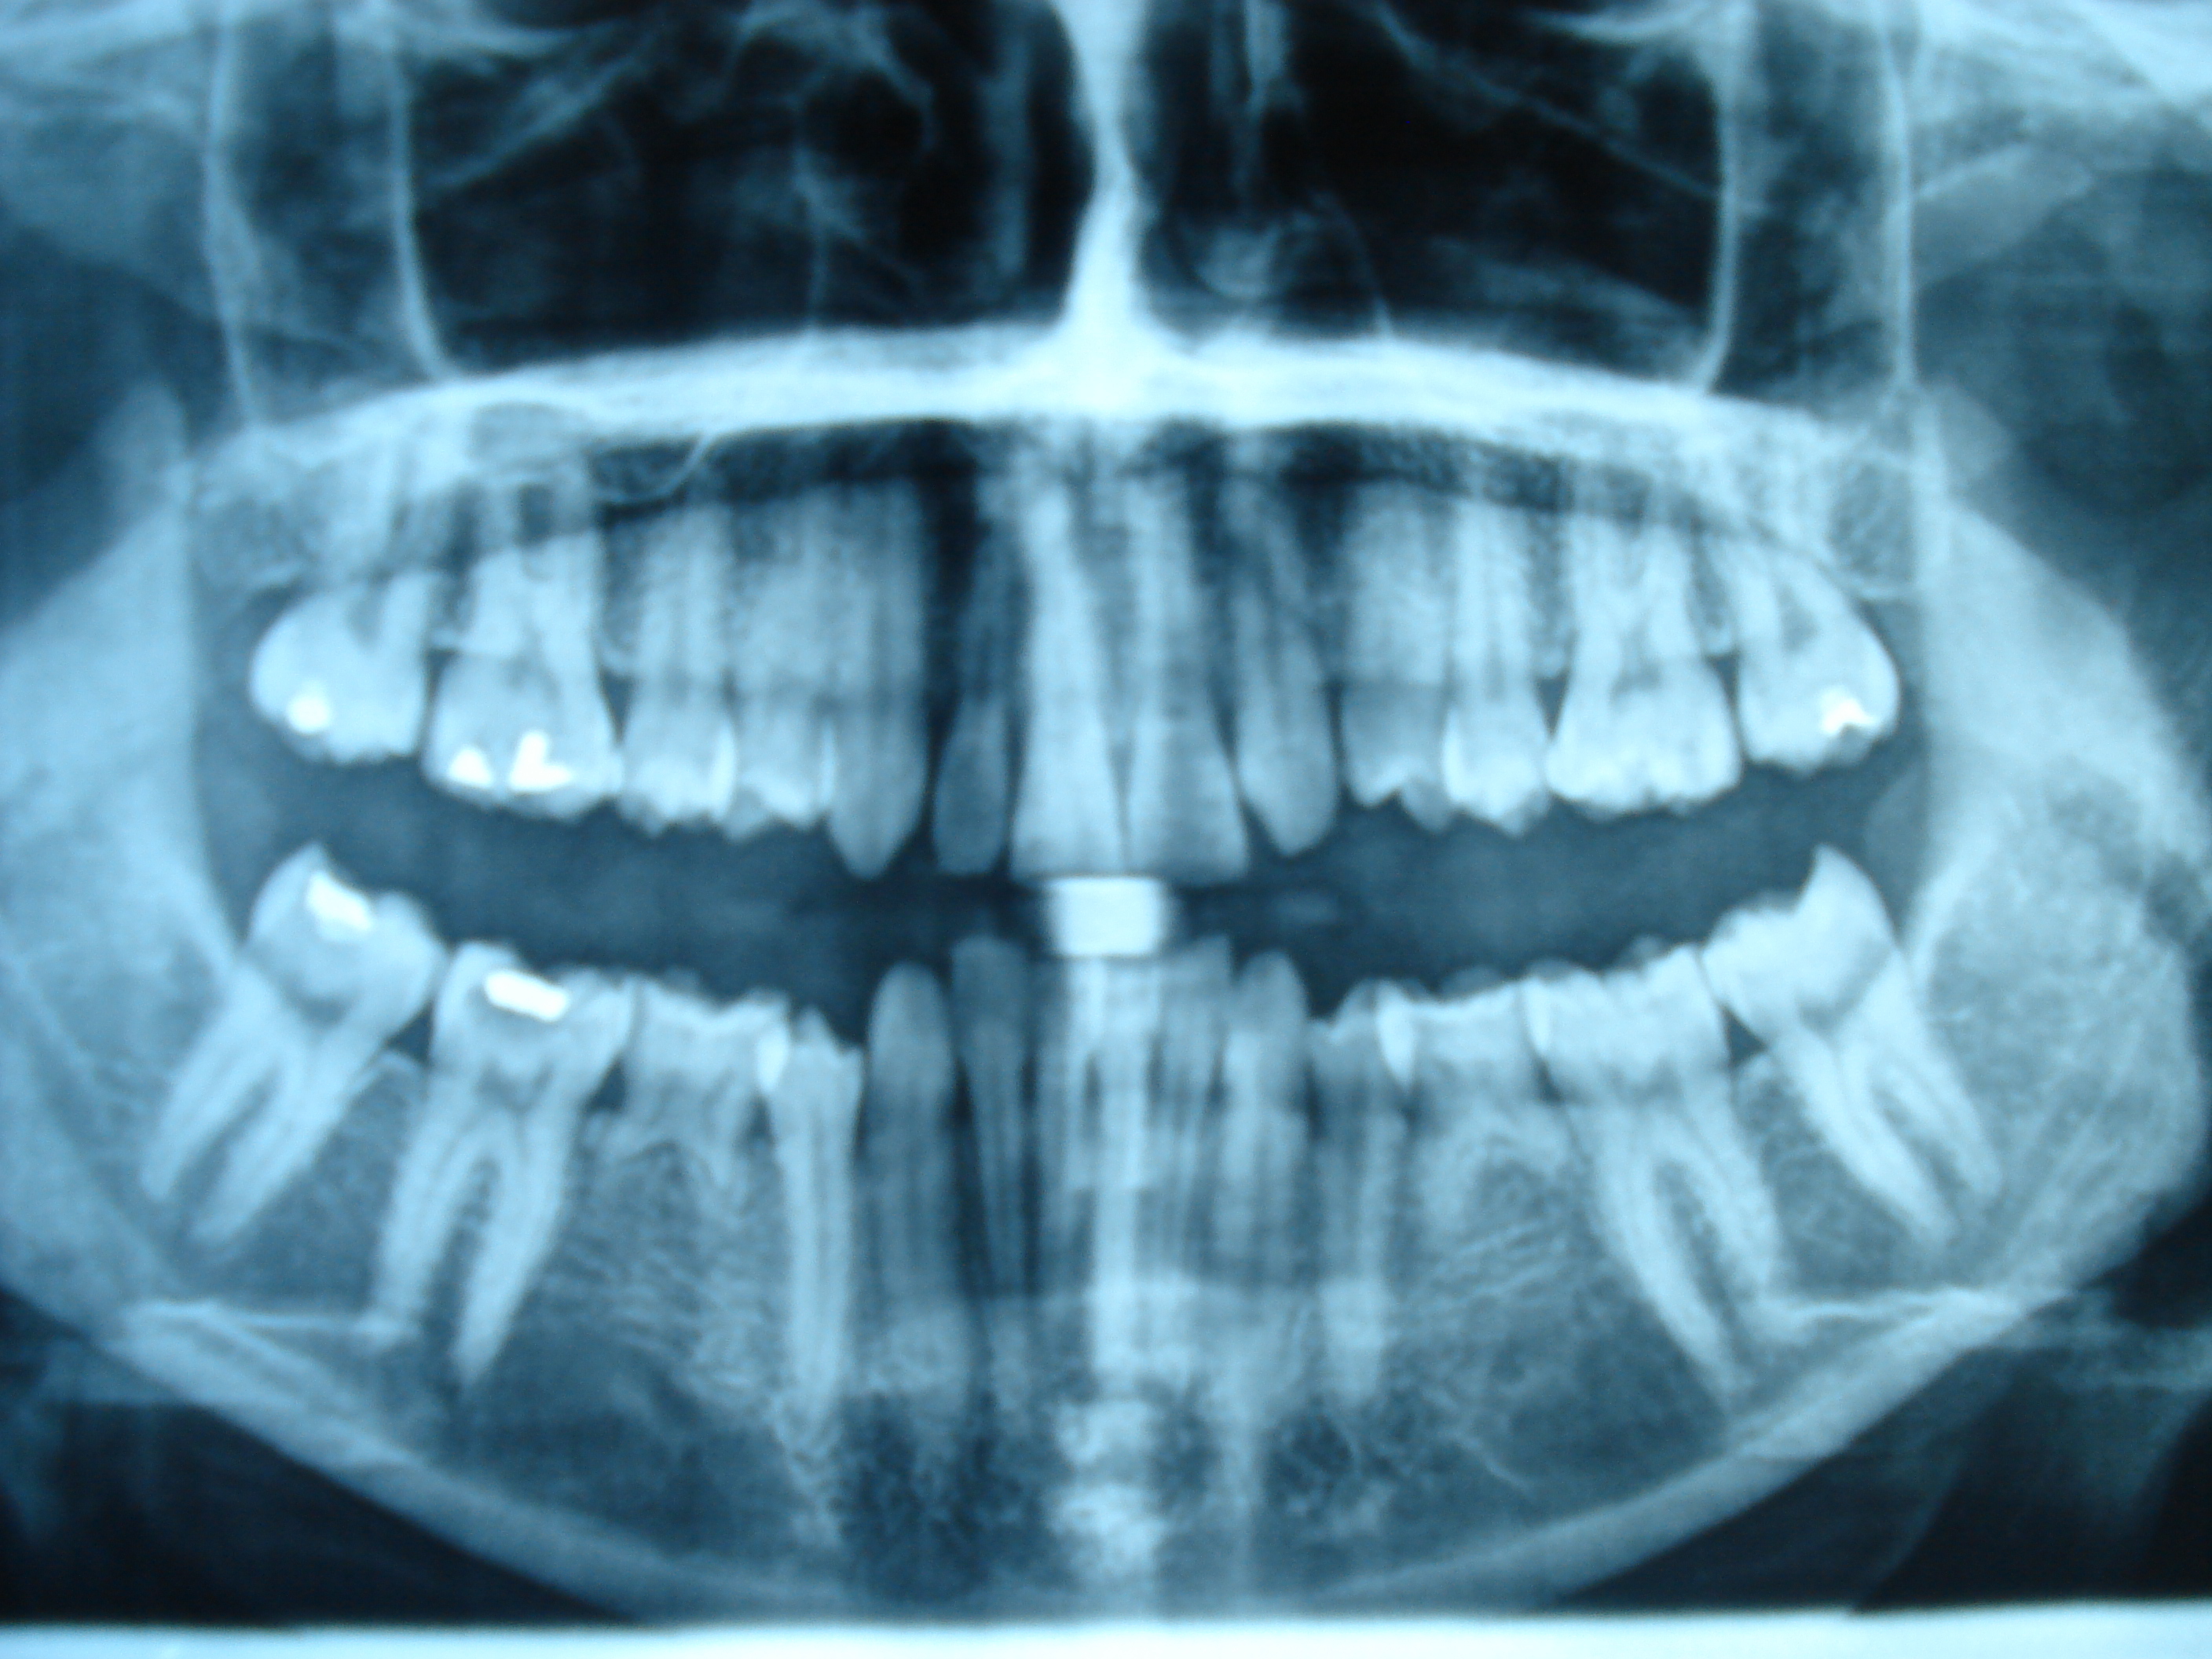

Clinical pattern were established using detailed history, clinical examination and radiographic evaluation of the affected subjects. Three generation pedigree were drawn and the mode of inheritance was established.

The clinical part of the study revealed the clinical and phenotypic profile of the disease condition in our local population.